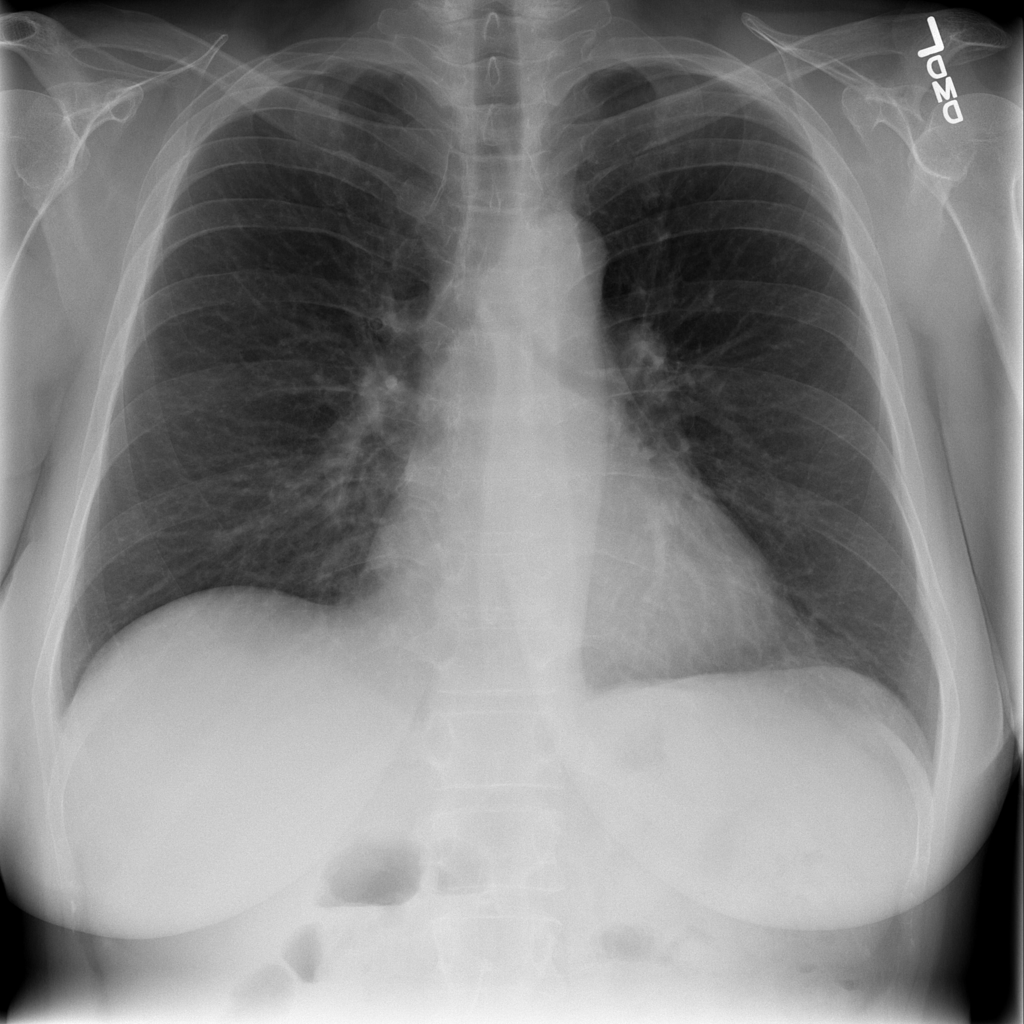

Showing up to 90 reference images for Pneumonia.

PAT-C0E5 · IMG-015Pneumonia

PAT-C0E5 · IMG-015

AP